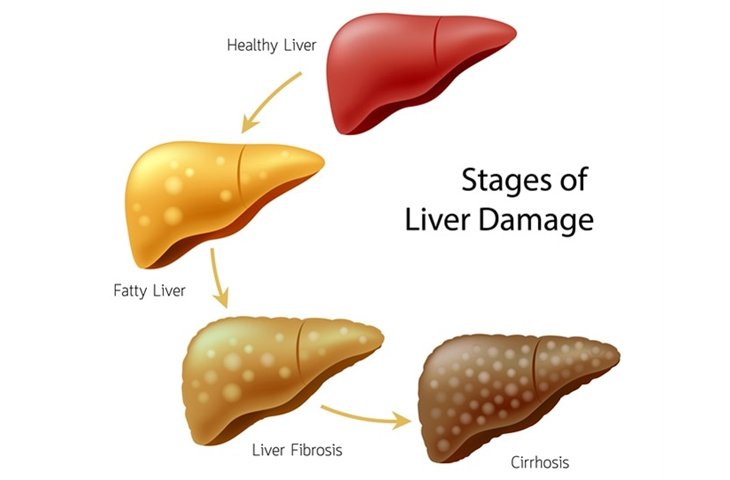

Liver cirrhosis

Liver cirrhosis is a slow-developing disease in which normal tissues of the liver are replaced by abnormal/scar tissues. The disease prevents the normal flow of blood through the liver and stops the liver from functioning properly, leading to a long-term damage. Cirrhosis even affects the abdominal blood vessels, and the huge portal vein, which transports blood from the intestines and spleen through the liver.

Cirrhosis causes ailments such as jaundice, excessive itching, and fatigue. Mild cirrhosis can be easily treated, but advanced stages may cause widespread liver damage.

Liver cirrhosis develops very slowly, and its symptoms can be identified at an early stage. Early stage liver cirrhosis is identified by symptoms such as:

Fatigue, Fever, Jaundice, Weight loss, Fluid retention, Black stools and bloody vomit.